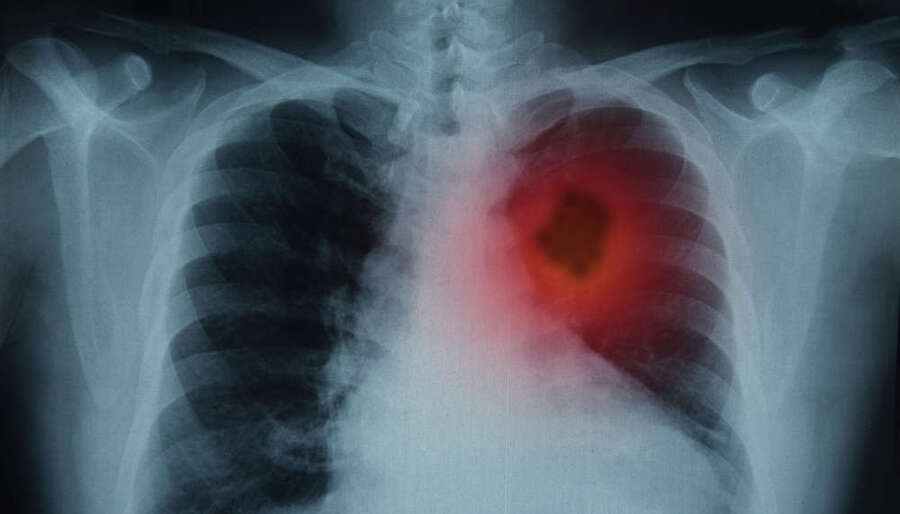

Ο καρκίνος του πνεύμονα παραμένει ένας από τους πιο θανατηφόρους τύπους καρκίνου, κυρίως επειδή συχνά διαγιγνώσκεται σε προχωρημένο στάδιο, όταν οι θεραπευτικές επιλογές είναι περιορισμένες. Στην Ελλάδα, όπως και σε μεγάλο μέρος της Ευρώπης, παρά την πρόοδο που έχει επιτευχθεί στο θέμα της πρόσβασης των ασθενών στη θεραπεία, εξακολουθούν να υπάρχουν προκλήσεις στην έγκαιρη διάγνωση, στην παροχή έγκαιρης φροντίδας και στην ισότιμη πρόσβαση σε καινοτόμες θεραπείες.

Είναι σημαντικό να αναγνωριστεί ότι ο καρκίνος του πνεύμονα δεν αποτελεί νόσο που προκαλείται από το ίδιο το άτομο και μπορεί να επηρεάσει οποιονδήποτε. Η αποτελεσματική αντιμετώπισή του απαιτεί να ξεπεράσουμε το στίγμα και να επικεντρωθούμε στην πρόληψη, την έγκαιρη διάγνωση και την ποιοτική φροντίδα για όλους. Οι βασικοί παράγοντες κινδύνου (όπως το κάπνισμα, το άτμισμα, η ατμοσφαιρική ρύπανση και η επαγγελματική έκθεση) αυξάνουν σημαντικά την πιθανότητα εμφάνισης καρκίνου του πνεύμονα. Η χρήση καπνού παραμένει η κύρια αιτία αποτρέψιμων θανάτων στην ΕΕ, με σχεδόν 500.000 θανάτους το 2021 και εκτιμώμενο κόστος 2,5% του ετήσιου ΑΕΠ της Ευρώπης.